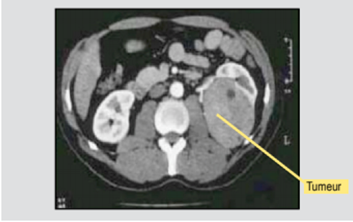

Le cancer du rein procède d’un processus particulier qui consiste en la transformation maligne du revêtement des cellules des tubules avec dans 80 % des cas une typologie d’adénocarcinome. On parle d’adénome à cellules claires ou tumeur de Grawitz.

Le cancer du rein se manifeste au départ par du sang dans les urines, des douleurs lombaires ou l’apparition d’une masse dans la région lombaire. Mais un certain nombre est de découverte fortuite à l’occasion d’examens d’imagerie médicale pratiqués pour d’autres raisons, notamment la réalisation d’un scanner thoracique dans le cadre du dépistage de lésions liées à l’amiante.